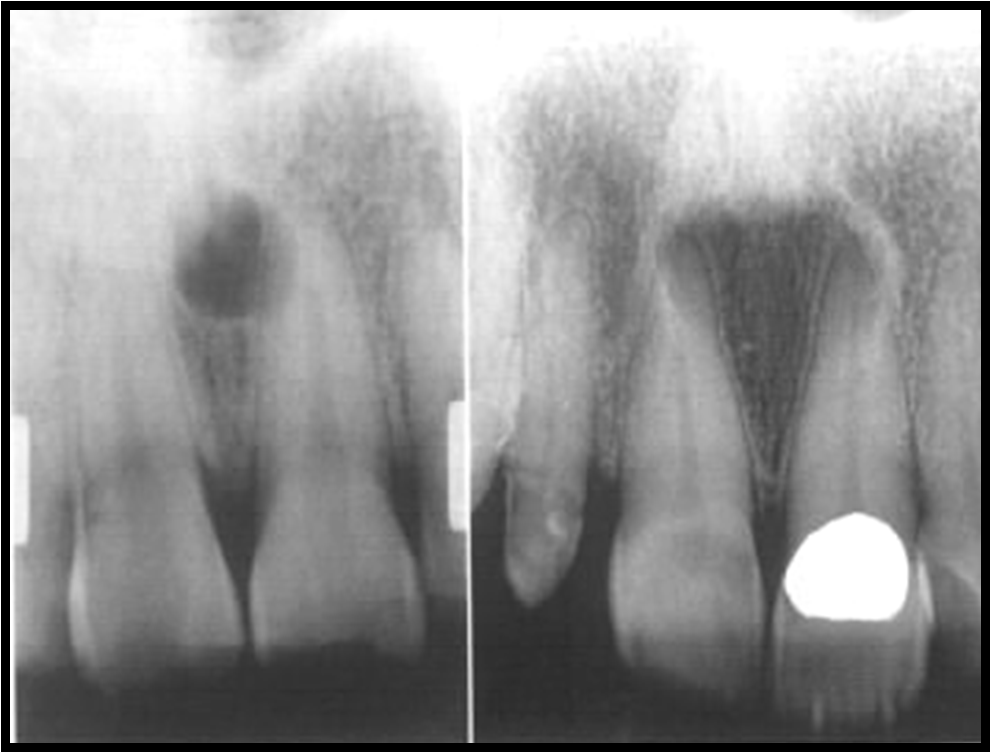

Solitary Bone Cyst Exodontia Oral Bone Cyst Aneurysmal bone cyst (abc) is rare benign lesions of bone which are infrequent in craniofacial skeleton. Solitary bone cyst (sbc), also known as a simple bone cyst, hemorrhagic cyst, or traumatic cyst is classified by the who among. Cystic lesions within the mandible can cause bony remodeling that can weaken the. Cysts of the oral region occur commonly owing to. Oral Bone Cyst.

Traumatic (Simple) Bone Cyst in a 10Year Old Patient Traumatic Oral Bone Cyst Cysts commonly occur in the mandible and appear as unilocular or multilocular radiolucencies on dental radiographs. Aneurysmal bone cyst (abc) is rare benign lesions of bone which are infrequent in craniofacial skeleton. A traumatic bone cyst is an uncommon nonneoplastic lesion of the jaws that is considered as a “pseudocyst” because of the lack. Solitary bone cyst (sbc), also known. Oral Bone Cyst.

periapical jaw tooth bony cyst lesion infection kazemi oral surgery 1 Oral Bone Cyst Sbc is predominantly diagnosed in first two decades of life. Here we report a case of solitary bone cyst mimicking a periapical cyst of. Cysts of the oral region occur commonly owing to the mouth's complex embryonic origins and frequency of inflammation. This article outlines the diagnostic features required for separating the most common of odontogenic cysts and select osseous. Oral Bone Cyst.